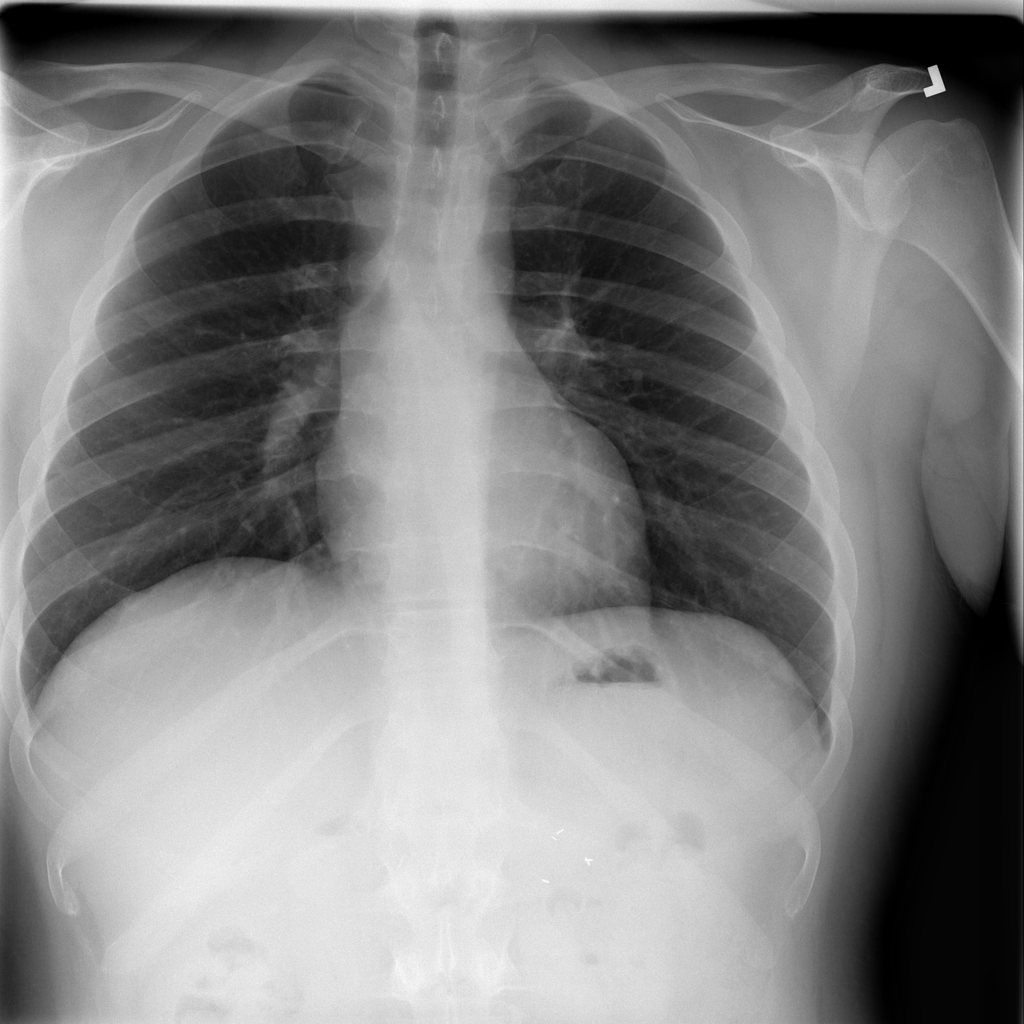

PAT-C1A7 · IMG-055Consolidation

PAT-C1A7 · IMG-055

AP